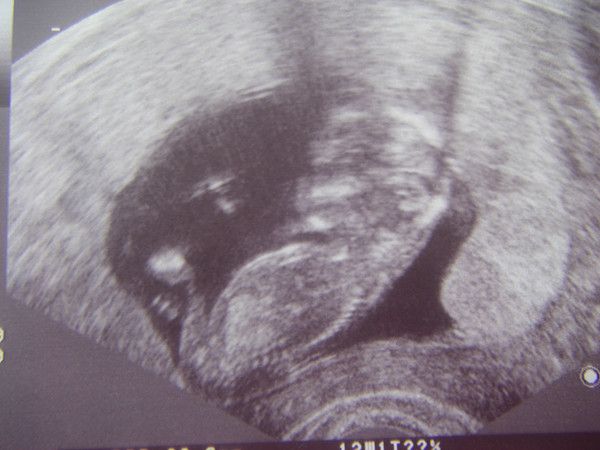

Club-Fotos

Hier sehen Sie alle Fotos dieses Clubs.